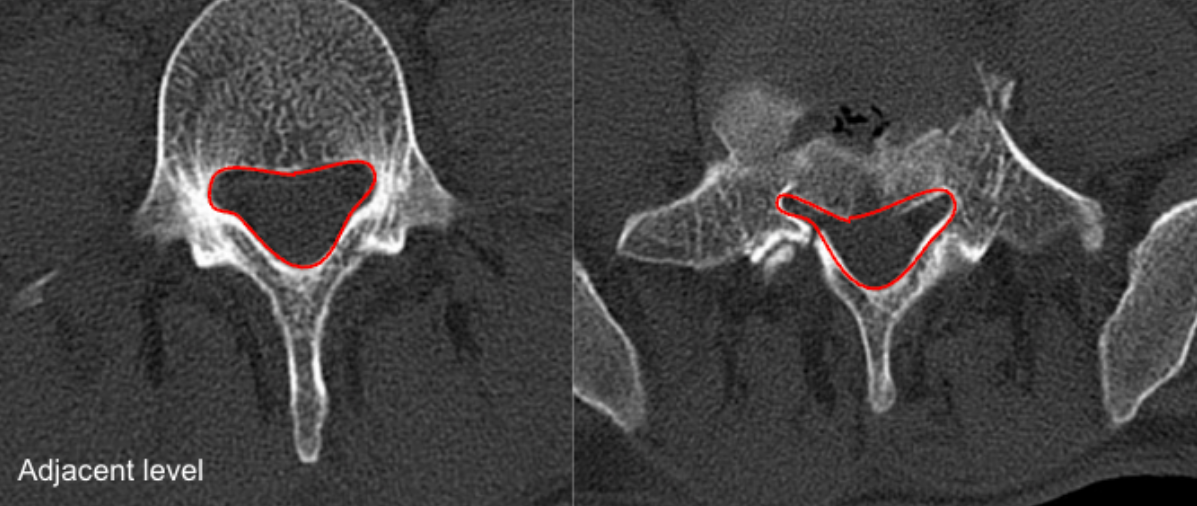

Cross-Sectional Area of Canal (CSA)

CT Scan

Lateral Recess Depth/Width